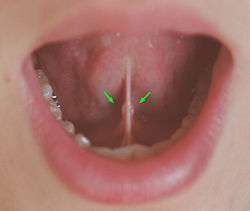

The sublingual caruncle is a small prominence on either side of the frenulum on the under surface of the tongue. They mark the site where the submandibular glands empty into the oral cavity via the submandibular duct (of Wharton).